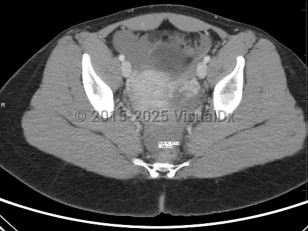

Ectopic pregnancies are found in reproductive-age patients. Risk factors include prior ectopic pregnancy, history of endometriosis or tubal infection (pelvic inflammatory disease), pregnancy occurring in the setting of current use of a progesterone intrauterine device (IUD), history of tubal surgery, advanced maternal age (aged 35 years or older at time of due date), and tobacco use. It is also important to note that over 50% of all patients diagnosed with an ectopic pregnancy have no known risk factors.

Presentation can vary. Patients may present with a positive home pregnancy test and unilateral lower quadrant pain that is often sharp / stabbing in nature. Some will present after tubal rupture and be hemodynamically unstable. Others may present with only vaginal spotting and be unaware they are even pregnant. Therefore, one must have a high index of suspicion when a patient arrives with a positive pregnancy test and symptomatology. As many as 18% of women presenting to the emergency department with first-trimester bleeding, pain, or both will be found to have an ectopic pregnancy.